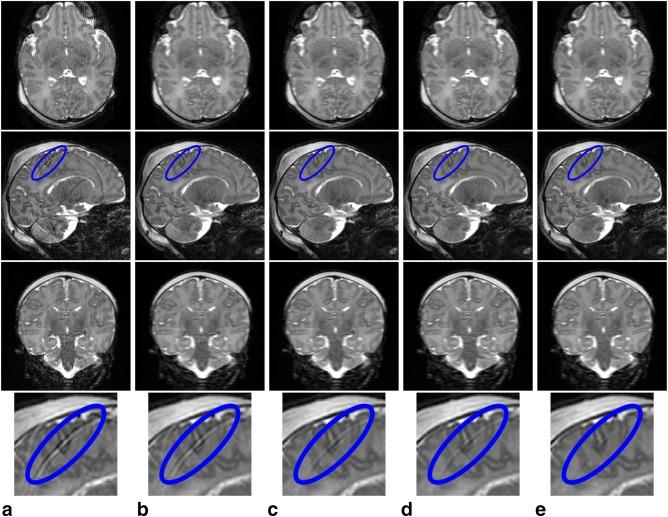

The method alternates between motion estimation and reconstruction using a common objective function for both. Estimates of three-dimensional motion states for each shot and slice are gradually refined by improving on the fit of current reconstructions to the partial k-space information from multiple coils. Overlapped slices and super-resolution allow recovery of through-plane motion and outlier rejection discards artifacted shots. The method is applied to T and T brain scans acquired in different views.

The procedure has greatly diminished artifacts in a database of 1883 neonatal image volumes, as assessed by image quality metrics and visual inspection. Examples showing the ability to correct for motion and robustness against damaged shots are provided. Combination of motion corrected reconstructions for different views has shown further artifact suppression and resolution recovery.

该程序大大减少了 1883 个新生儿图像体积数据库中的伪影,通过图像质量指标和视觉检查进行评估。提供了示例,展示了校正运动和对损坏拍摄具有鲁棒性的能力。对不同视图的运动校正重建进行组合,进一步显示出对伪影的抑制和分辨率的恢复。